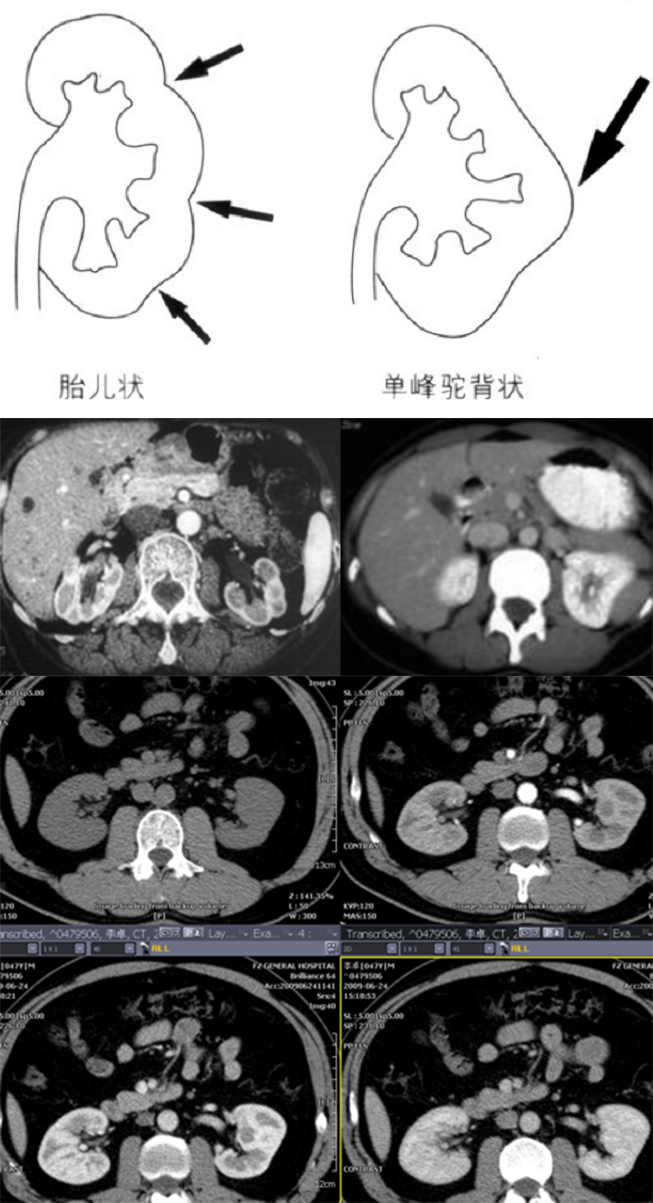

肾形态异常包括融合肾和分叶肾、驼峰肾和肾柱排列异常

肥大肾柱:系从皮质延续到肾盂、肾锥体之间的皮质柱

驼峰肾:系肾表面局限隆突,类似驼峰,大部分为脾脏压迫所致

分叶肾又称胎儿性分叶肾,50% 成人不同程度存在,由于胚胎时肾叶融合不完全,肾表面有浅沟,浅沟处则有自皮质向内伸入的肾柱

以上均为正常解剖变异